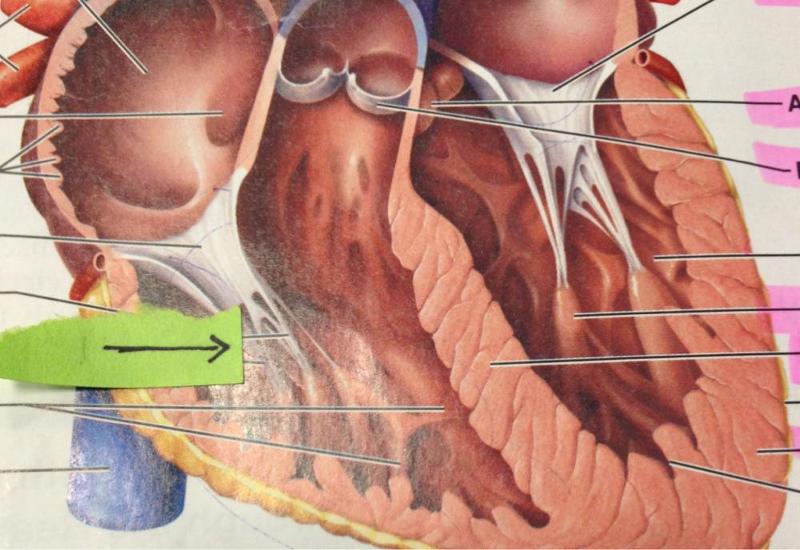

Chordae tendineae

Endocardium

Epicardium

Left atrioventricular (=bicuspid, =mitral) valve

Left/right atrium

Left/right auricle

left/right ventricle

Myocardium

Papillary muscles

Pectinate muscles

Right atrioventricular (=tricuspid) valve